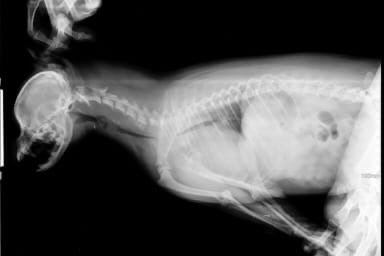

Мочекаменная болезнь (МКБ), или уролитиаз — это не просто «камни в почках», как многие думают. Это хроническое обменное заболевание, при котором в мочевыводящих путях вашего питомца — в почках, мочеточниках или, что самое частое и опасное, в мочевом пузыре и уретре — образуется «песок» (мелкая взвесь) или настоящие камни (уролиты). Представьте себе, как в перенасыщенном растворе выпадают кристаллы соли. Примерно то же происходит в моче кошки при нарушении обмена веществ. Эти твердые образования травмируют нежную слизистую оболочку, вызывая боль и воспаление, а главное — могут привести к закупорке (обструкции) уретры, что является угрожающим жизни состоянием, требующим экстренной операции.

Почему это особенно опасно для котов?

У котов уретра (трубка, выводящая мочу из мочевого пузыря) очень длинная, узкая и имеет характерный S-образный изгиб. Именно здесь чаще всего происходит закупорка песком или слизистой пробкой. У кошек уретра шире и короче, поэтому у них мочекаменная болезнь чаще протекает в форме цистита (воспаления) без обструкции, но это не значит, что болезнь менее серьезна.

Не все камни одинаковы. У кошек чаще всего встречаются два основных типа, и от этого кардинально зависит стратегия лечения и диеты

Струвиты (трипельфосфаты)

Составляют около 50-60% случаев. Чаще образуются в щелочной моче. Имеют тенденцию образовываться относительно быстро, иногда в виде песка или мелких камней, которые могут растворяться при помощи специальной лечебной диеты, подкисляющей мочу. Чаще встречаются у кошек молодого и среднего возраста

Оксалаты кальция

На их долю приходится 30-40% случаев. Образуются в кислой моче. Эти камни очень твердые, растут медленно, и их невозможно растворить диетой. Основной метод лечения — хирургическое удаление. Более характерны для кошек старшего возраста, персов, гималайцев